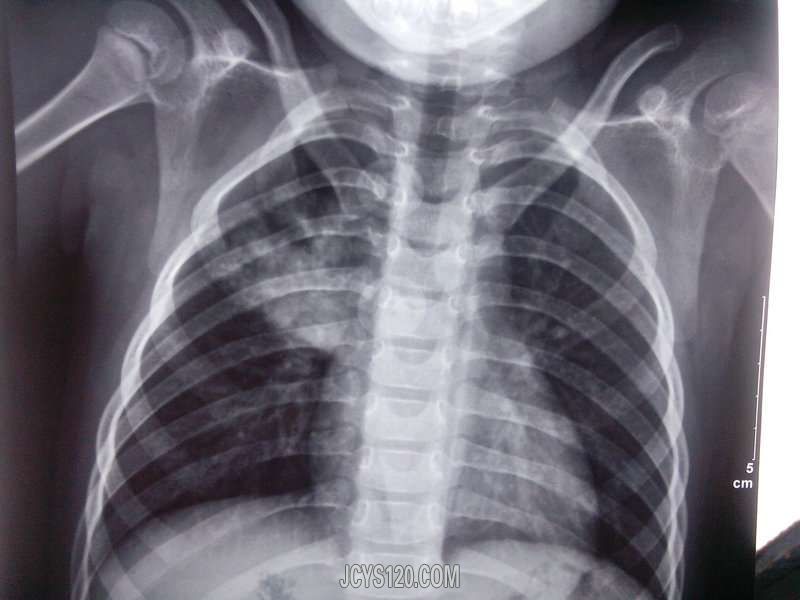

2小时前发热就诊,体温在家自测39°c,来诊后查体咽红充血,双肺呼吸音粗,未闻及干湿罗音,因为患儿服药困难所以给予输液治疗,头孢他啶、炎唬宁、利巴韦林三组液体,口服萘普生退热,液体用完,热退,第二天复诊,述回家后半夜体温再次升高到39°c,口服退烧药后下降至正常,考虑感冒,病程所致,没有调整方案,继续治疗,期间查体未发现有较前加重的症状,第五天为了明确诊断,建议患儿去医院检查,结果回报吓了一跳,右上肺炎(具体见胸片),调整治疗方案,给予青霉素、痰热清静滴5天,阿奇霉素5天,期间体温还是一直反复,建议患者住院治疗,住院后给予阿奇霉素(连续使用5天停三天,再用5天)头孢西丁等药物治疗,总时间24天才得以痊愈。第一次遇到病程这么长的,自认为期间的抗生素、激素的使用还算合理及时,不过真是想不通为什么会这样?无独有偶,接下来的一段时间连续遇到好几例,症状都差不多,因为前面的经验,发热两天后稍有咳嗽的,就建议胸片检查,还真查出好几例肺炎患儿。。。大家有遇到的吗?病程如此之长为何? [align=center] [/align]